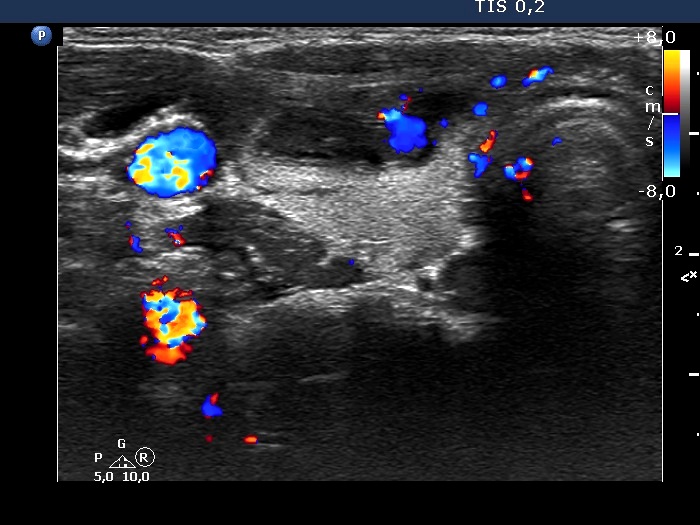

Examination 4 years later (ultrasonographic picture 9)

Right lobe, transverse scan, color Doppler mode - after aspirating 20 mL brown fluid. The vascularization is not specific.